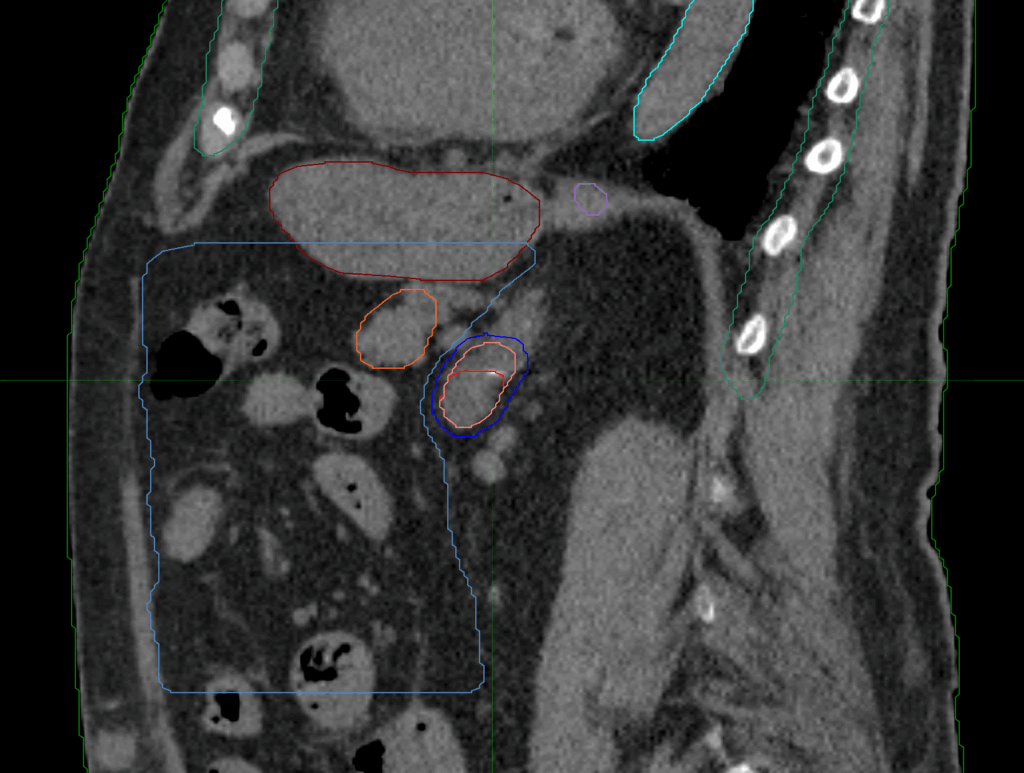

Planning CT Images